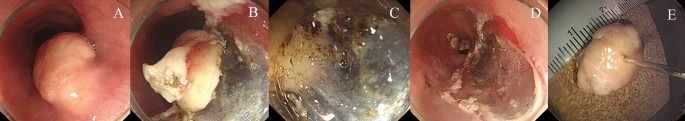

Underwater endoscopic mucosal resection for a 6-mm-sized esophageal granular cell tumor. A broad-based, round subepithelial tumor (SET) with whitish-to-yellowish overlying mucosa is seen in the lower esophagus (A). After filling the lumen of the esophagus with distilled water (B), electrosurgical snaring is performed without submucosal injection (C). The ulcer bed after endoscopic resection (D). An en-bloc resection was achieved (E).